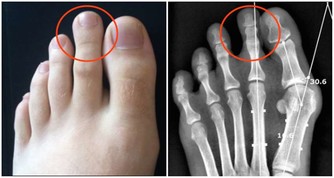

*****3.眼球表面出現異樣*****

脂肪沉積也會影響到眼球,患者虹膜之外會出現一圈灰色的環狀物,對視力不會造成影響。在40歲以上的人群中,約有45%的人會出現這種症狀;而在60歲以上的群體中,這一比例高達70%。目前已有研究證實這種“脂肪環”與某些誘發冠心病的危險因素有關。